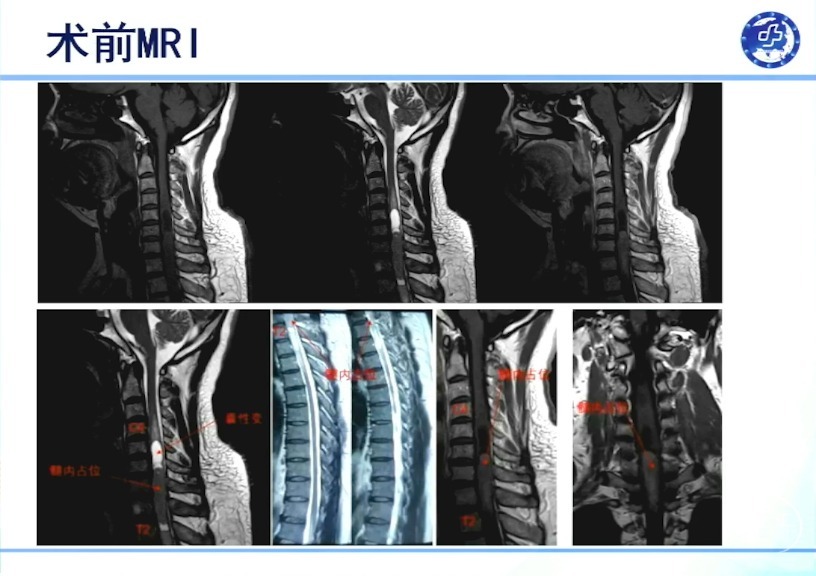

影像学